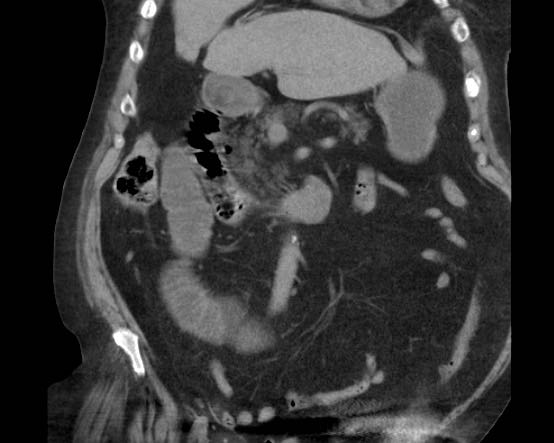

Đây là hình ảnh điển hình của tắc ruột do sỏi mật.

Lưu ý mức độ khó khăn khi phát hiện viên sỏi không vôi hóa.